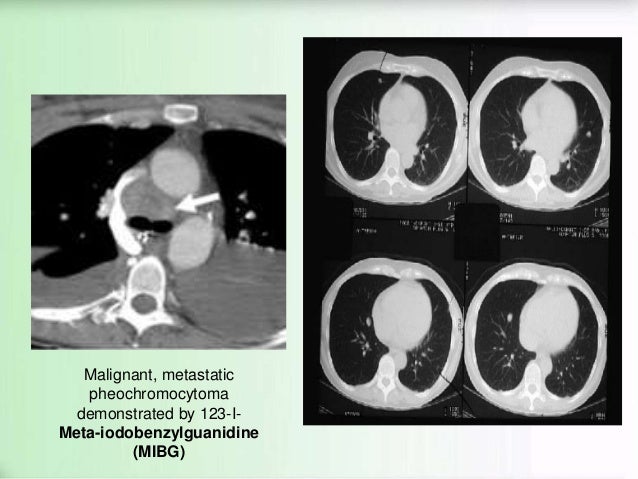

Reply

12. 12. Malignant, metastatic pheochromocytoma demonstrated by 123-I- Meta-iodobenzylguanidine (MIBG)